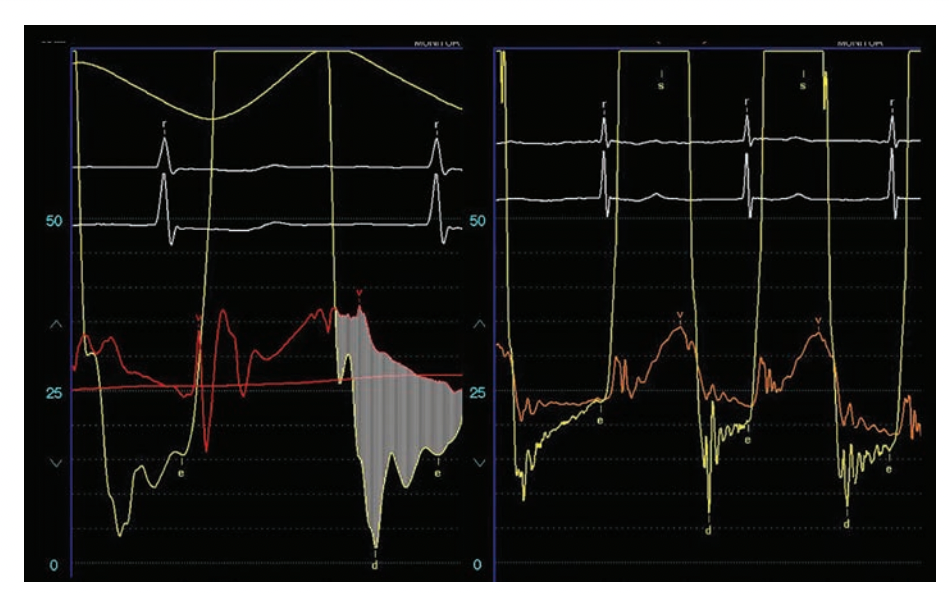

In general, the stenotic mitral valve area (MVA) can be measured in several ways (Figure 2).6 With confidence in the echocardiographic data, patients may be suitable for balloon valvuloplasty to open the stenotic valve and permit adequate cardiac output, and keep pulmonary hypertension at bay. At times, with equivocal data, exercise hemodynamics in the cath lab may be necessary. For best pressure and gradient data, use direct LA pressure from a transseptal approach rather than the pulmonary capillary wedge pressure (Figure 3). However, when pulmonary capillary wedge pressure is low and normal, it provides an effective first-line tool to screen for significant mitral valve gradients.

PBMV results in a gradient decrease of 50% or more, and a valve area increase to 1.5 cm2, the definition of success in the majority of the literature. In ideal valve anatomy, the mitral valve area will typically increase to 1.8 cm2 or more. Examples of the hemodynamic changes occurring in the pressure wave forms for a patient with MS before and after mitral balloon valvuloplasty are shown on Figure 4.